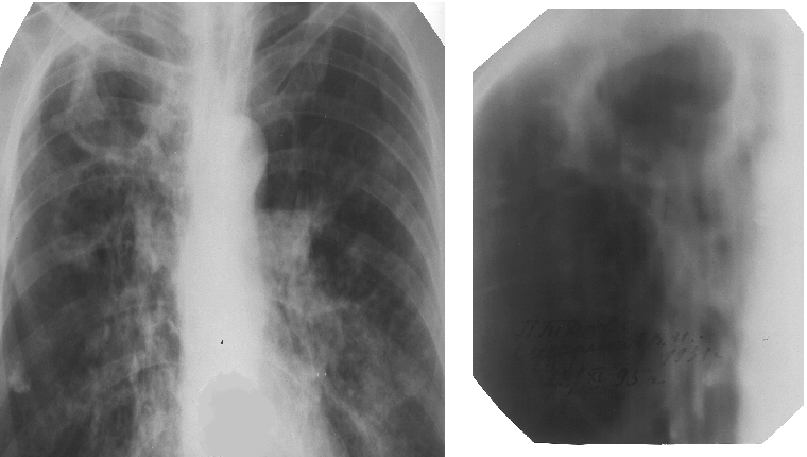

$$$012

Больной, 40 лет, обратился с жалобами на отеки в области лодыжек, боли в правом подреберье, тошноту, слабость. Болеет туберкулёзом легких в течение 5 лет. Бактериовыделение непостоянное. Диуретики дают кратковременный эффект. Рентгенограмма (1) и томограмма (2) легких представлены. В ОАК: гемоглобин 115г/л, эритроциты 3,4х1012/л, лейкоциты 11х109/л, СОЭ 40 мм/ч. В ОАМ: белок 1,33%, гиалиновые цилиндры. В биохимическом анализе крови: креатинин 126ммоль / л, АлАт 1,2 мккат/л, билирубин 32 ммоль/л, общий белок 50г/л. Поставьте диагноз и выберите оптимальное лечение:

A)Фиброзно–кавернозный туберкулез верхней доли правого легкого в фазе инфильтрации. Амилоидоз почек. Витамины, муколитики, диуретики

B)Цирротический туберкулез легких в фазе инфильтрации. Амилоидоз почек. Диуретики, белковые препараты, кардиотоники

C)Фиброзно-кавернозный туберкулез верхней доли правого легкого в фазе обсеменения. Амилоидоз внутренних органов. Гепатопротекторы, белковые препараты, диуретики

D)Цирротический туберкулез верхней доли правого легкого в фазе обсеменения. Амилоидоз внутренних органов. Гепатопротекторы, витамины, диуретики

E)Фиброзно–кавернозный туберкулез верхней доли правого легкого в фазе обсеменения. Амилоидоз печени. Витамины, муколитики, Гепатопротекторы, диуретики

{Правильный ответ}=C